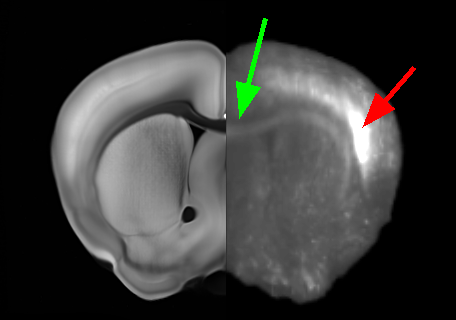

For registration, each CLARITY volume I0subscript𝐼0I_{0} was downloaded from the NeuroData cluster. They were resampled to a 50 μm𝜇𝑚\mu m resolution and registered to ARA atlas image J1subscript𝐽1J_{1} with 12-parameter affine alignment under MI matching. Deformable registration was then done with MI-LDDMM as implemented in ndreg. A cascaded-α𝛼\alpha approach was adopted in which a smoother registration with α=0.05𝛼0.05\alpha=0.05 was followed by registrations at α=0.02𝛼0.02\alpha=0.02 and α=0.01𝛼0.01\alpha=0.01 to refine the results (Fig. 2). Both ARA-aligned CLARITY volumes and CLARITY-aligned ARA annotations were uploaded to the NeuroData cluster. This allowed us to visualize ARA annotations overlaid on the terabyte-scale CLARITY images (Fig 1). Deformable registration was done with SSD-LDDMM and Mask-LDDMM to demonstrate the advantages of MI-LDDMM. For validation MI-LDDMM was also compared to SyN ANTs [1] with MI cost and σ=1.0𝜎1.0\sigma=1.0 mm Gaussian regularization (Fig. 3).

Refer to caption

(c) MI- LDDMM

Figure 3: Comparison of SSD-LDDMM (3(a)), Mask-LDDMM (3(b)), MI-LDDMM (3(c)) and SyN ANTs (3(d)) registration of CLARITY volume. Panes (3(a)-3(d)) have an ARA coronal slice on the left juxtaposed to the corresponding aligned CLARITY slice on the right. Green arrows point out that the corpus callosum is misaligned by SSD-LDDMM but aligned correctly by MI matching. Red arrows show that SSD-LDDMM distorts bright regions. Fiducial landmarks were manually placed in the corpus callosum, and midbrain of the acquired volumes. Pane (3(e)) compares mean errors between the deformed CLARITY and ARA landmarks after registration.